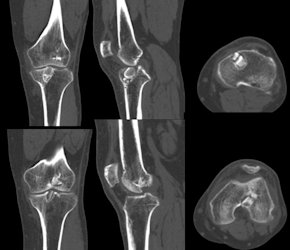

Eğer doktorunuz revizyon cerrahisine karar verdi ise ciddi bir ameliyat öncesi planlama gereklidir. Dikkatli bir muayene ile eşlik edebilecek yan bağ yaralanmaları, menisküs hasarları, kas gücü, önceki yara izleri ve ilk cerrahide kullanılmış olan dokular değerlendirilir. Ardından röntgen grafileri ile eklemin genel durumu, tünel yerleşimleri, kullanılan implantlar ve dizinizdeki kıkırdak aşınmasının miktarı değerlendirilir. Bacaklarınızda bir kemik eğriliği varsa bunun için aks grafisi adı verilen kalça, diz ve ayak bileği eklemini içine alan boy grafileri çekilebilir. İlk cerrahide açılan tünellerde genişleme varsa, bu revizyon sırasında kullanılan dokuların kemiğe tespitini olumsuz etkileyecektir, şüpheli bir durumda tünel genişlemesi bilgisayarlı tomografi ile değerlendirilebilir. Son olarak manyetik rezonans görüntüleme ile dizinizdeki bütün yumuşak doku ve kemik yapılar ayrıntılı olarak incelenir.Bütün bu incelemeler sonrasında doktorunuz revizyon cerrahisinin şeklini, kullanılacak olan doku kaynaklarını, tek veya iki aşamada mı cerrahi yapılacağını, menisküs, kıkırdak ve diğer bağlarınıza bir işlem gerekip gerekmediğini ve kemik dizilimini düzeltecek ameliyatlara ihtiyacınızı belirler. Son olarak yapılan artroskopik inceleme ile eklem içi yapılar değerlendirilir ve yapılacak işlemin devamının nasıl olacağına karar verilir (Resim 3)

Çoğu durumda tek bir cerrahi işlem ile revizyon ön çapraz bağ cerrahisi yapılabilir, ancak nadir de olsa iki aşamalı revizyon gerekli olabilir. Birden fazla cerrahi gereken durumlar aşağıdaki gibidir;- İlk cerrahi sırasında açılan tünellerde ileri derecede genişleme var ve revizyon sırasında yeni bağın tespiti mümkün değilse iki aşamalı cerrahi yapılabilir. Önce tüneller, vücudun başka bir bölgesinden alınan kemik parçaları ile doldurulur ve iyileşmesi beklenir. Altı ay sonra yeterli kemik oluştuktan sonra revizyon yapılır (Resim 4)

Resim 4: İlk cerrahi sonrası tünel genişlemesi saptanan hastaya ait görüntüler.